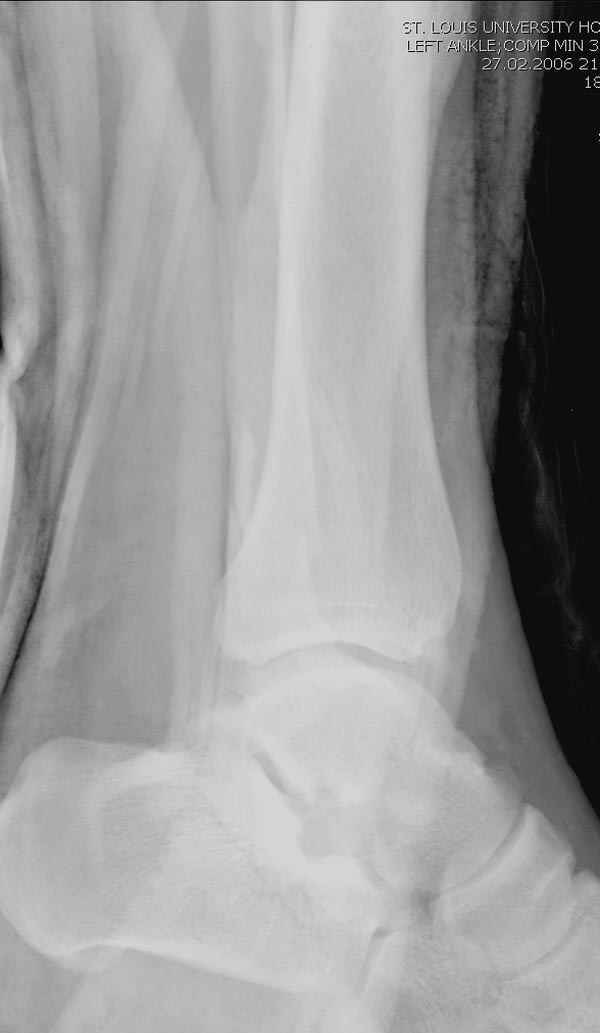

Тему неоднократно разбирали (см. архив), как всегда, недостаточны ренгенологические исследования - кроме прямого и боковых снимков, еще нужна косая ренгенограмма для определения ankle mortise, без мортиз снимка трудно определить высоту и ротацию малоберцовой. (снимки)

Ренгенология даст ответ как классифицировать перелом, на сегодня применяется классификация “Lauge Hansen fracture classification SER supination-external rotation или supination-eversion classification Danis

Weber А, В, С.”

Показания для фиксации: укорочения и ротация малоберцовой, особенно обращают внимание на любой подвывих таранной кости: неустраненый подвывих впоследствии приводит к раннему артрозу. Задний край фиксирует тогда, когда перелом составляет около 25% суставной поверхности голеностопного сочленения и смещение более 2мм.

По снимку ваш случай относится к Weber В, фиксацию производят восстановлением длины малоберцовой кости, под ренгеном (ЭП)контролем, для этого я предпочел бы латеральный доступ, остеотомия по линии перелома, удлинение малоберцовой засчет скоса линии остеотомии, компрессия “lag technique”по линии остеотомии и фиксацию провести латеральной пластиной. Отдельный задний доступ, остеотомия по линии перелома, репозиция и фиксация заднего края вашим предпочтительным методом: 3.5мм шурупом с шайбой или пластиной Antiglide Butress

Djoldas Kuldjanov, MD

Department of Orthopedic Surgery

St. Louis University Medical Center